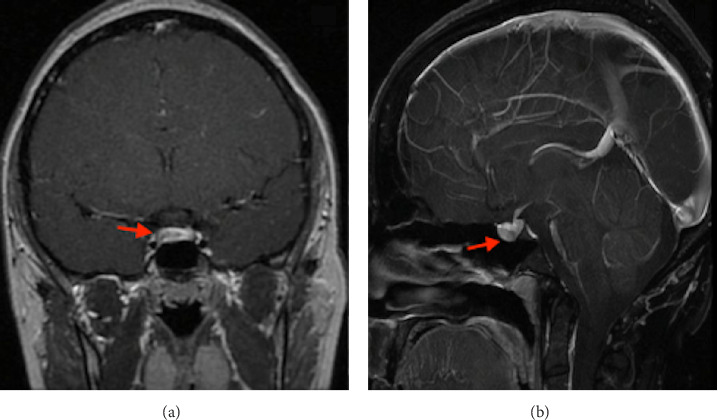

催乳素瘤是垂体腺瘤中最常见的亚型,是导致女性闭经和不孕的主要病因之一。主要的治疗方法需要使用多巴胺激动剂,有效地恢复生育能力。在微泌乳素瘤的病例中,在怀孕期间出现症状性肿瘤扩大的可能性非常低,估计只有2.4%。因此,一旦成功怀孕,停用多巴胺激动剂,并对患者的病情进行持续的临床监测。妊娠期脑垂体中风的发生率极为罕见。我们提出一个病例29岁的患者与微泌乳素瘤,治疗卡麦角林,这是停止在实现怀孕。然而,在妊娠第16周,她出现了持续的头痛和视力下降,表现为左颞偏视。非对比磁共振成像(MRI)显示腺瘤增大,并伴有出血的迹象。她在怀孕26周时被转介到我们医院。卡麦角林治疗恢复,患者耐受良好。剂量增加到每周2毫克,因为双颞偏视没有改善。妊娠35周进行的非对比MRI扫描显示腺瘤尺寸进一步增大,尺寸为17 × 21 × 13 mm,并有瘤内出血的迹象。在妊娠39周进行了有计划的剖宫产手术,没有遇到母胎并发症。由于腺瘤压迫交叉,没有开始母乳喂养。因此,继续使用多巴胺激动剂治疗。在产后随访期间,患者经历了月经周期恢复,催乳素水平正常化,肿瘤大小缩小。最终,诊断确定为微泌乳素瘤,在怀孕期间由于垂体瘤中风而扩大。虽然微泌乳素瘤在妊娠期间通常具有较低的症状性肿瘤生长风险,但本病例强调了警惕的临床监测对迅速发现和处理这种罕见并发症的重要性。这个例子作为一个不常见事件的教育例子-微泌乳素瘤在怀孕期间经历中风。

Prolactinomas are the most prevalent subtype of pituitary adenomas and represent one of the leading etiological factors responsible for amenorrhea and infertility in women. The primary therapeutic approach entails the use of dopamine agonists, which effectively restore fertility. In cases of microprolactinomas, the likelihood of experiencing a symptomatic enlargement of the tumor during pregnancy is exceptionally low, estimated at a mere 2.4%. Consequently, once pregnancy is successfully achieved, the administration of dopamine agonists is discontinued, with ongoing clinical monitoring of the patient's condition. The incidence of pituitary apoplexy during pregnancy is exceedingly rare. We present a case of a 29-year-old patient with microprolactinoma, treated with cabergoline, which was discontinued upon achieving pregnancy. However, at the 16th week of gestation, she presented with persistent headaches and compromised visual acuity, manifesting as left temporal hemianopia. A noncontrast magnetic resonance imaging (MRI) revealed an enlargement of the adenoma, accompanied by evidence of hemorrhage. She was referred to our hospital at 26 weeks of gestation. Cabergoline treatment was reinstated and well tolerated by the patient. Doses were increased to 2 mg per week because bitemporal hemianopia was not improving. A subsequent noncontrast MRI scan performed at 35 weeks of gestation demonstrated a further increase in adenoma size, measuring 17 × 21 × 13 mm, with signs of intratumoral bleeding. A planned cesarean section was performed at 39 weeks of gestation, without encountering maternal-fetal complications. Breastfeeding was not initiated due to the adenoma's compression of the chiasm. Accordingly, dopamine agonist therapy was continued. During the postpartum follow-up, the patient experienced a resumption of menstrual cycles, normalization of prolactin levels, and a reduction in tumor size. Ultimately, the diagnosis was established as a microprolactinoma, which had enlarged during pregnancy due to a pituitary tumor apoplexy. Although microprolactinomas typically carry a low risk of symptomatic tumor growth during pregnancy, this case emphasizes the critical importance of vigilant clinical monitoring to swiftly detect and manage this rare complication. This instance serves as an educational example of an uncommon event-a microprolactinoma experiencing apoplexy during pregnancy.